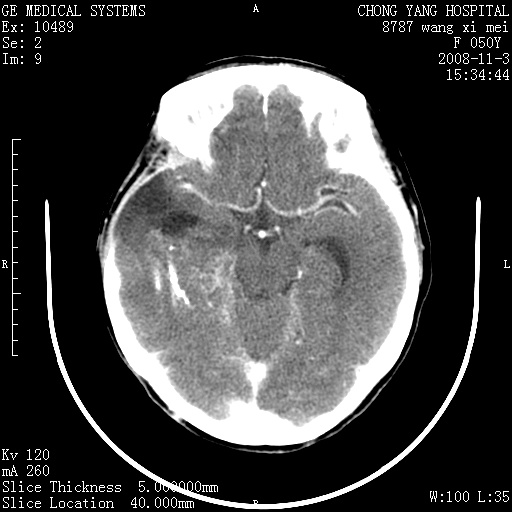

右颞骨局限性缺如,局部脑组织无外隆。右颞叶可见片状脑脊液样低密度影,边缘较清,右侧侧脑室三角区可见一块状等密度影,且伴有强化,余未见明显异常改变。

考虑:右大脑术后改变伴肿瘤复发。

手术后局部片状低密度改变(软化灶),其后方颞叶似等密度病灶,界限不清,内见钙化,有轻度占位效应,但增强后强化之血管走行如常。应不考虑:复发!

应考虑肿瘤复发,右颞顶叶已出现轻度强化肿块.必要时可与原片比较以下.

局部软化灶并钙化;无花边样强化,不象复发